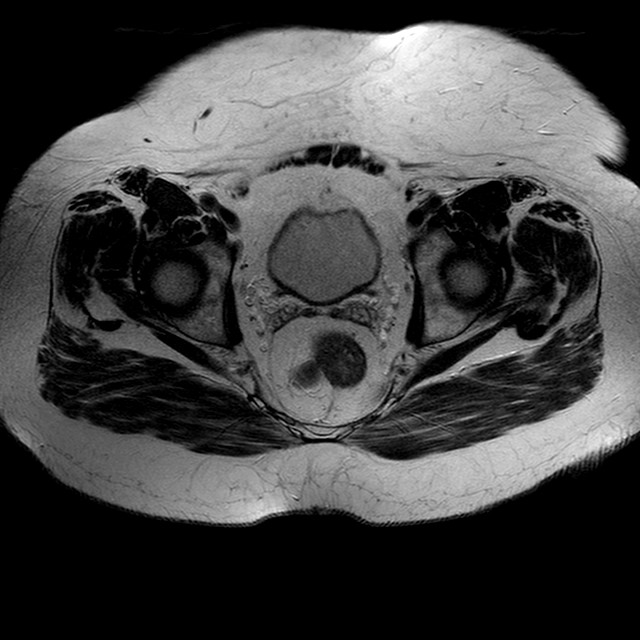

Esami: RMN BACINO

T2w TSE

Evidenti e simmetriche alterazioni osteofitosiche in regione coxo femorale con riduzione delle rime articolari. Degenerazione completa del cercine glenoideo. Non attuali segni di versamento articolare. Non segni di edema osseo che escludono attuale algodistrofia od osteonecrosi. Lieve e simmetrica riduzione del trofismo della muscolatura glutea.